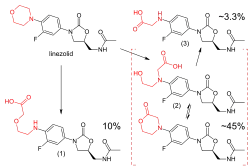

Линезолид метаболизируется в печени путём окисления морфолинового кольца без участия системы цитохрома Р450. Этот метаболический путь приводит к образованию двух крупных неактивных метаболитов (что каждый приходится около 45 % и 10 % дозы выделяется в устойчивом состоянии), одного малого метаболита и нескольких следовых метаболитов, ни один из которых приходится более 1 % выделяется дозы.[82] Клиренс линезолида зависит от возраста и пола; он самый быстрый у детей (на долю которого приходится более короткий период полураспада) и, вероятно, на 20 % ниже у женщин, чем у мужчин.[1][82][83]